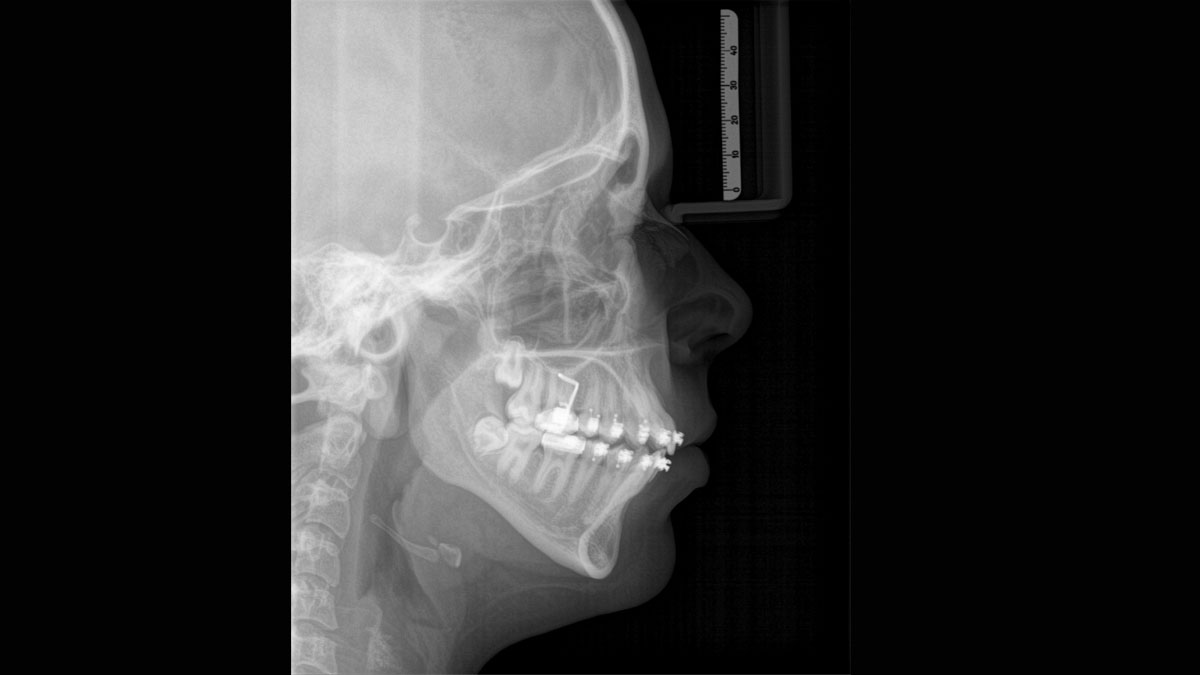

Para obtener imágenes panorámicas excepcionales con alta nitidez. Puede elegir un brazo cefalométrico derecho o izquierdo opcional, que puede reacondicionarse en cualquier momento

Gracias al modo de dosis baja optimizado con un filtro exclusivo, es posible obtener radiografías de estructuras densas, como huesos, a una dosis enormemente reducida. Esto hace que la dosis baja inteligente sea una opción atractiva y eficiente para muchas situaciones clínicas. Ya sea en ortodoncia o implantología, con el equipamiento Dentsply Sirona encontrará la configuración óptima para cada caso.